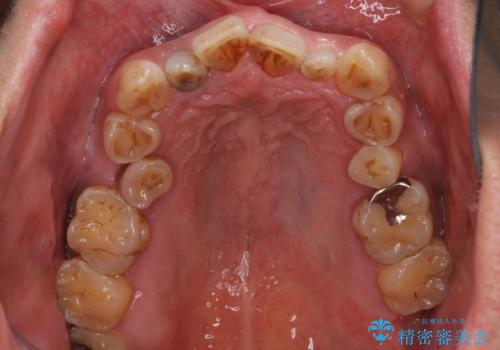

- 骨格的な咬み合わせのズレ、前歯のデコボコとクロスバイトを気にして来院された患者様です。

全額的にデコボコが強いため、上下左右の小臼歯計4歯を抜歯し、ワイヤー装置による矯正治療を行うこととしました。

抜歯する歯の一部をセオリーである第一小臼歯ではなく、第二小臼歯にすることで、骨格的なずれをカバーするように計画しました。

小臼歯の抜歯する部位を選択したことで、安定した咬み合わせとなりましたが、第二小臼歯を抜歯した部分はスペースを閉じるのに長い期間を要しました。

矮小歯であった上顎前歯2本は、矯正治療後にバランスの取れた大きさのオールセラミッククラウンを装着しました。